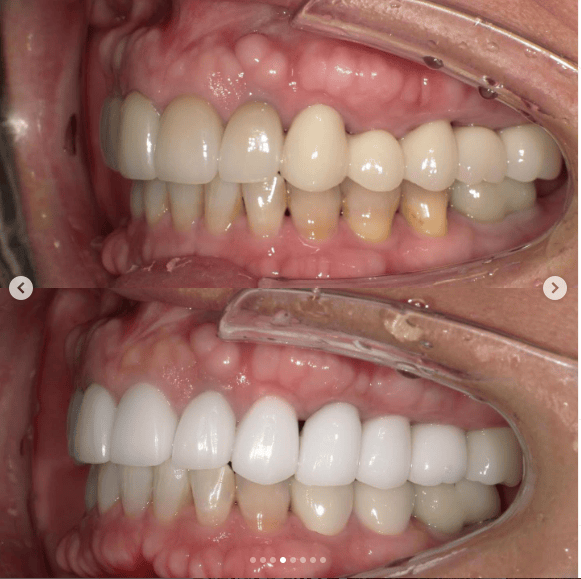

Case022 – インプラント

広島からの患者様です。

前歯を綺麗にしたい。インプラントをしたい。

という主訴で東京の歯医者をいろいろ調べて当院を選んでくださいました。

毎回、遠い中しっかり通ってくださり、選んで頂けた嬉しさと、その気持ちに応えたいという想いで診療させて頂きました。

前歯はご希望のお色でラミネートベニアでは出せない透明感のあるセラミックに上下左側7はインプラントをさせて頂きました。

左上は破折で温存不可。

骨も少なかったので、サイナスリフトも行い計五回の来院で被せ物を入れさせて頂きました。

左下は前回のクリニックでの埋入位置が深すぎて食べカスも毎回詰まる、セルフメンテナンスではら汚れも取れない。インプラント周囲炎にもなっていたので、一度前のインプラントを除去し、そこから新しくインプラントを埋入し、診療させて頂きました。

インプラント、歯並び、審美歯科にご興味のある方はいつでも相談にお越しください。

担当 理事長 佐藤 悠野